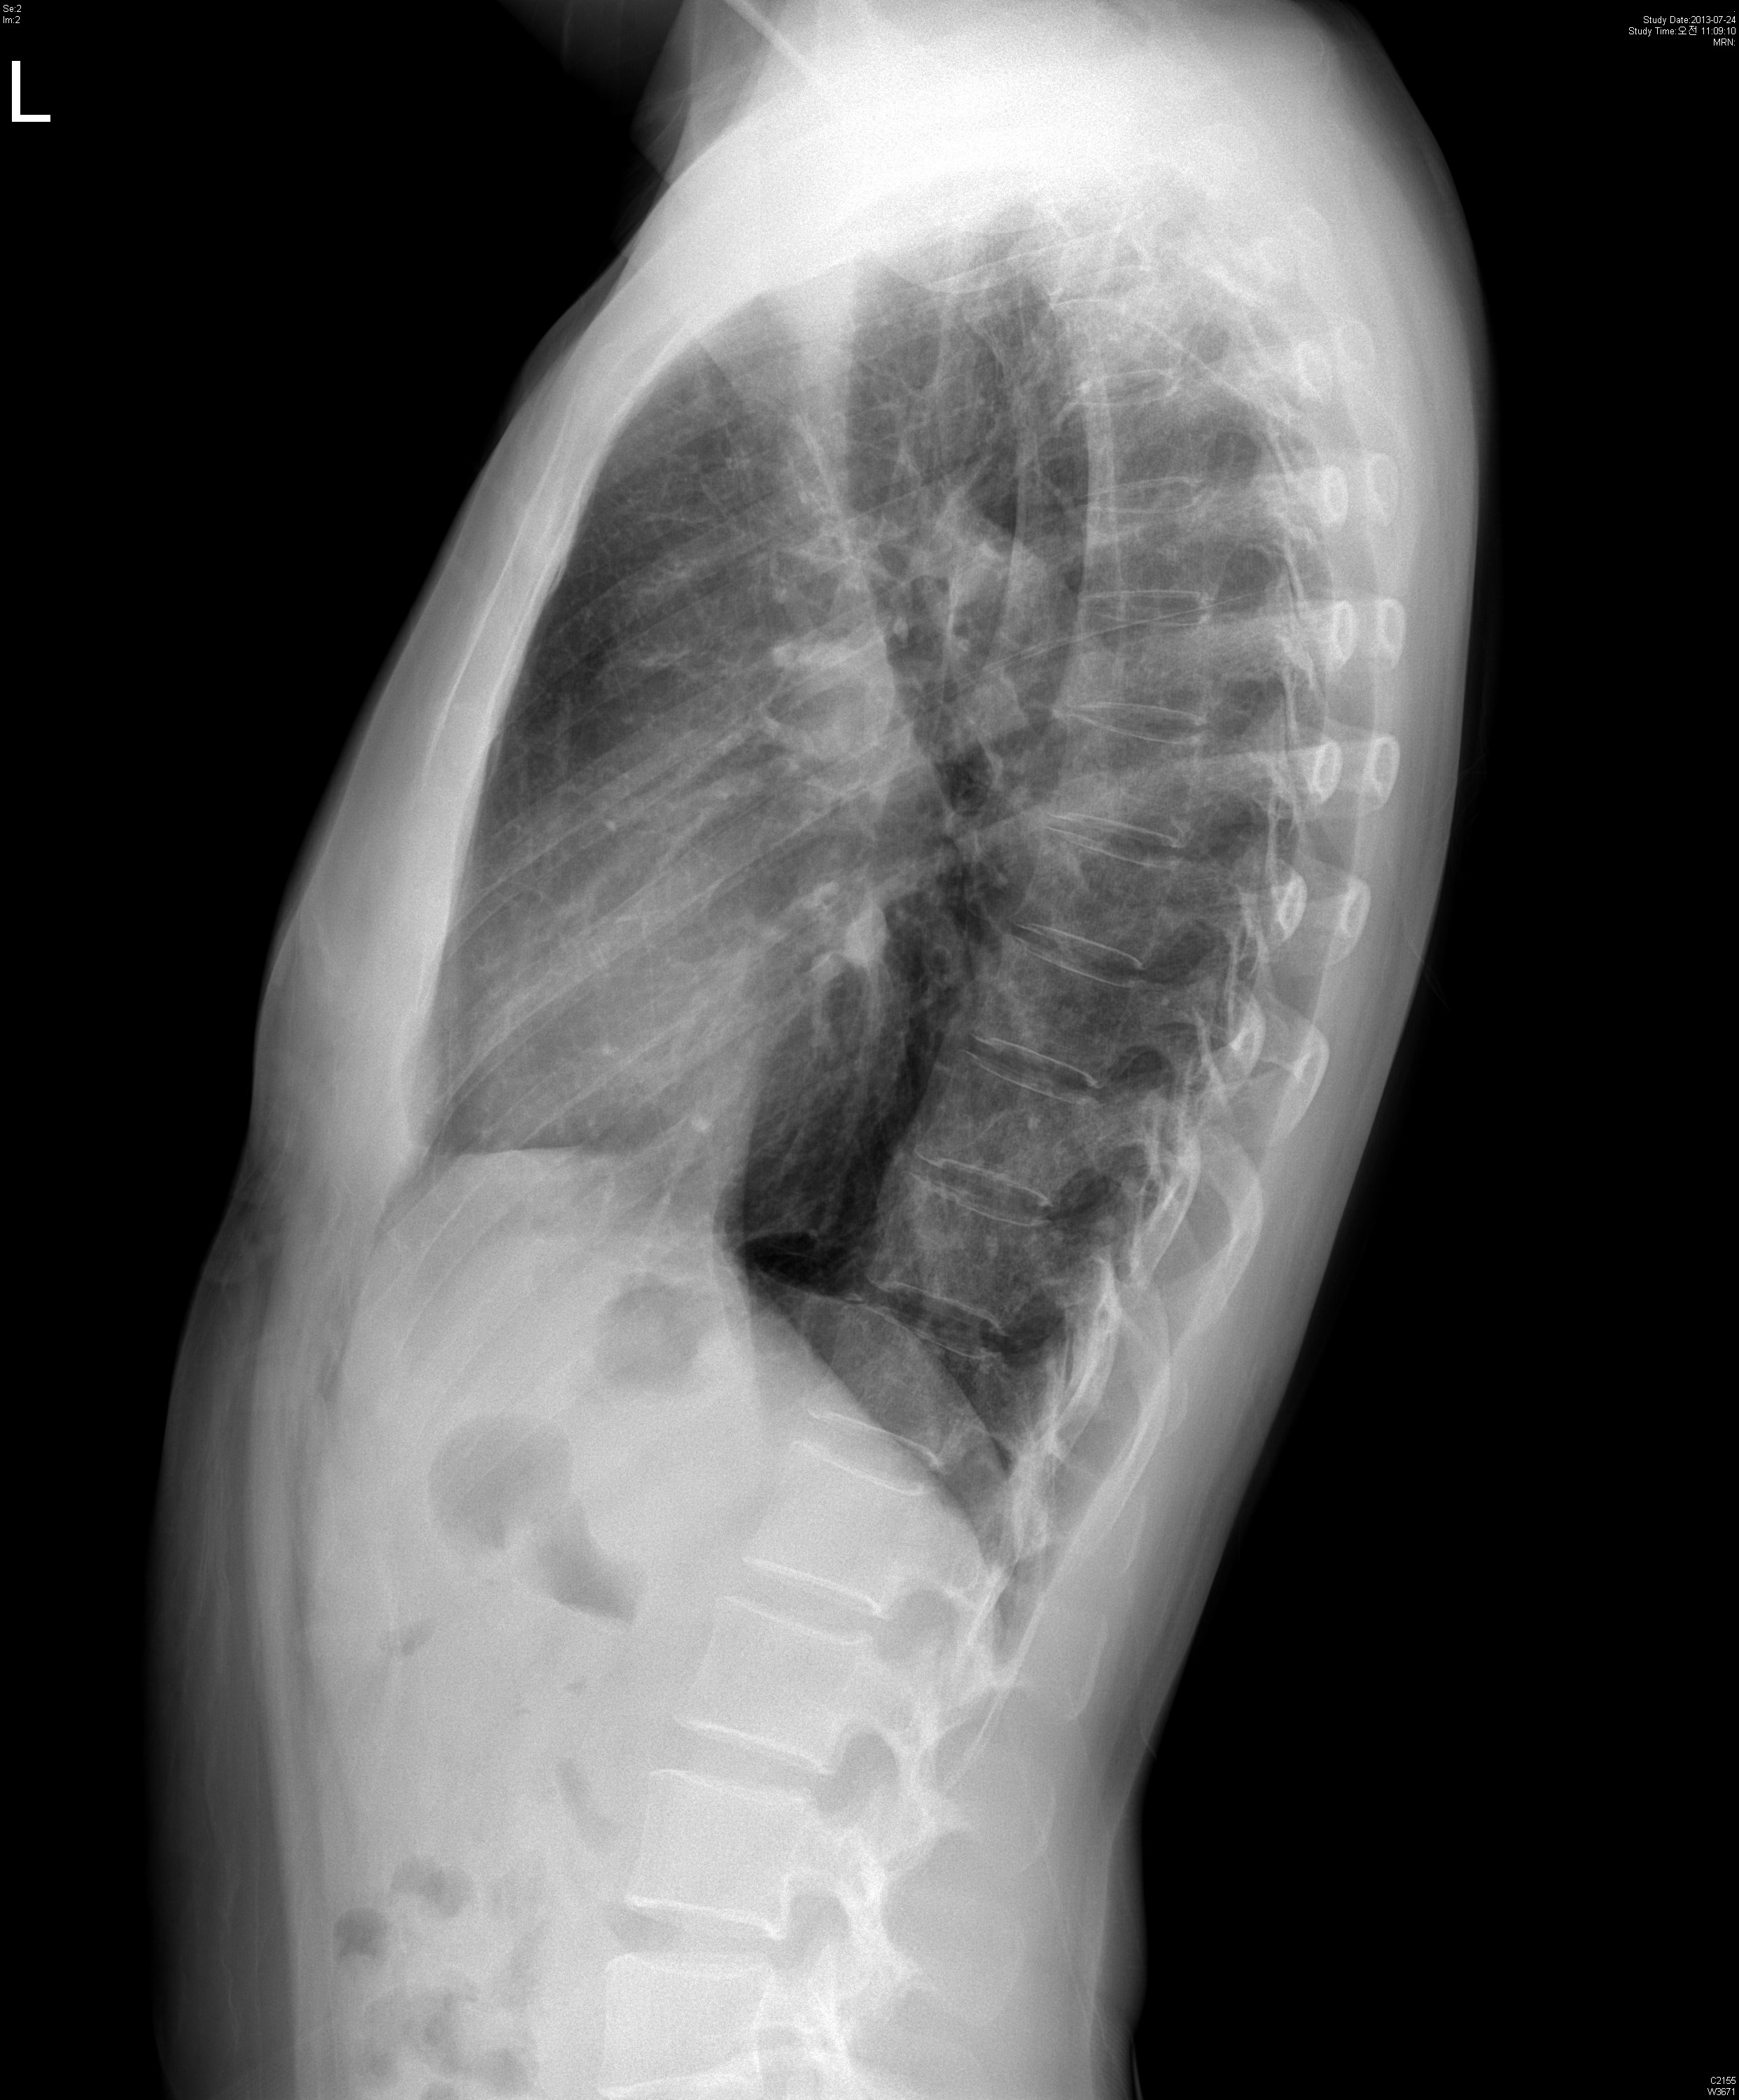

45¼¼ ¿©ÀÚ. chronic coughÀÖ´ø ºÐÀ¸·Î hemoptysis·Î ¿Ü·¡ ³»¿ø.

CXR»ó °üÂûµÇ´Â ¼Ò°ß ȤÀº º´¸í ´äº¯ÁÖ¼¼¿ä.